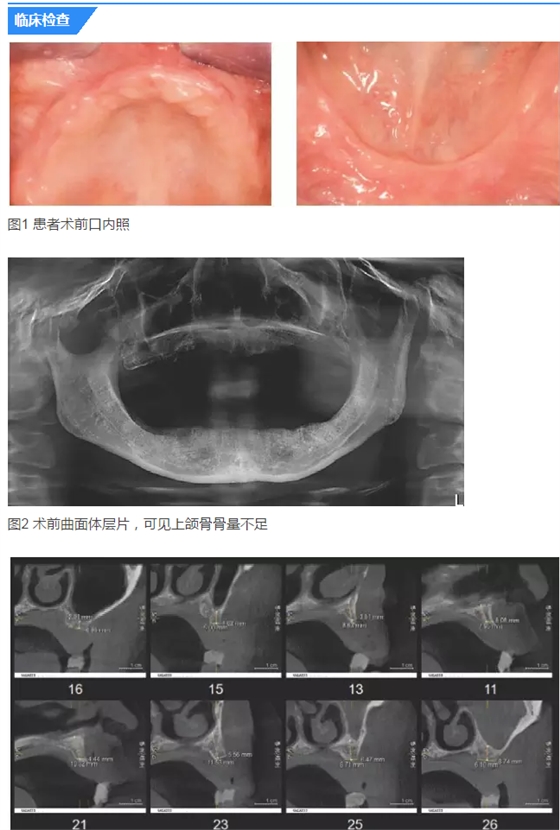

患者女,42歲。1年前因牙周病拔除全口牙齒,行全口活動(dòng)義齒修復(fù),現(xiàn)自覺(jué)影響咀嚼和生活來(lái)診。要求:牙種植修復(fù)后即刻可使用。